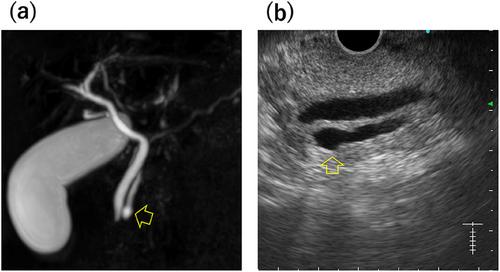

Wirsungocele, a cystic dilation at the end of the main pancreatic duct, is associated with recurrent acute pancreatitis. A 52-year-old man presented to our hospital with recurrent epigastric pain over an 8-month period with a history of multiple medical visits for the same complaint. Endoscopic ultrasound (EUS) and magnetic resonance cholangiopancreatography (MRCP) revealed focal cystic dilatation at the end of the main pancreatic duct; thus, he was diagnosed with Wirsungocele. He underwent endoscopic pancreatic sphincterotomy and 5Fr 4 cm pancreatic duct stent placement; the pancreatic duct stent was removed 1 month later. Magnetic resonance imaging performed 3 months after discharge revealed no cystic dilation, and he has had no recurrence of pancreatitis for at least 6 months. Dysfunction of the sphincter of Oddi, weakening of the pancreatic duct wall, inflammation and recurrent stress, elevated intraductal pressure, and genetic and structural factors are suspected mechanisms behind the pathophysiology of Wirsungocele. Although the etiology of Wirsungocele is not known, its timely identification and treatment are critical to preventing recurrent episodes of pancreatitis. This case demonstrates the diagnostic value of combining MRCP and EUS as well as the therapeutic benefits of endoscopic intervention, including sphincterotomy and stent placement, in managing Wirsungocele-associated recurrent pancreatitis. Given the paucity of reports on recurrent pancreatitis due to the Wirsungocele, we herein report this case and review the literature.